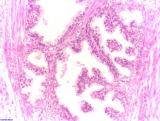

Die Prostata ist eine Drüse mit Ausführungsgängen in die Harnröhre. Sie besteht aus 30 bis 50 Einzeldrüsen. Diese produzieren ein Sekret, das bei der Ejakulation in die Harnröhre abgegeben wird und sich dort mit den Spermien vermischt. Das Sekret macht beim Mann etwa 30% des Ejakulates aus. Durch seinen pH-Wert von 6,4 erhöht es die Überlebenschancen der Spermien, da die Vagina zum Schutz vor Infektionen sauer ist. Zum anderen enthält das Prostatasekret biogenes Amin, welches bewegungsauslösend auf die Spermien wirkt. Des Weiteren wird aus der Prostata das prostataspezifische Antigen (PSA) ausgeschüttet. Dadurch wird das Ejakulat dünnflüssiger. Das PSA ist ein wichtiger Bestandteil bei Laboruntersuchungen für Prostataerkrankungen (insbesondere Prostatakrebs)

Die in Deutschland weit verbreiteste und von Krankenkassen auch getragene Untersuchungsmöglichkeit ist der Tastbefund. Hierbei wird die Prostata rektal durch den Enddarm, welcher direkt an den Prostata vorbeiführt, ertastet auf bösartige Veränderungen untersucht. Der Urologe prüft hierbei auf Knotenbildung im sonst weichen Prostatagewebe. Die Tastuntersuchung wird von vielen Männern als unangenehm empfunden und unter anderem dadurch zu der Tatsache, das der Prostatakrebs die dritthäufigste Todesart bei Männern in Deutschland ist, da viele den Schritt zur Vorsorgeuntersuchung beim Urologen scheuen.

Werden beim Tastbefund negative Veränderungen vom Urologen wahrgenommen wird auch mittels Laboruntersuchung das sog. PSA (prostataspezifisches Antigen) hergenommen um weitere diagnostische Punkte abzustecken.